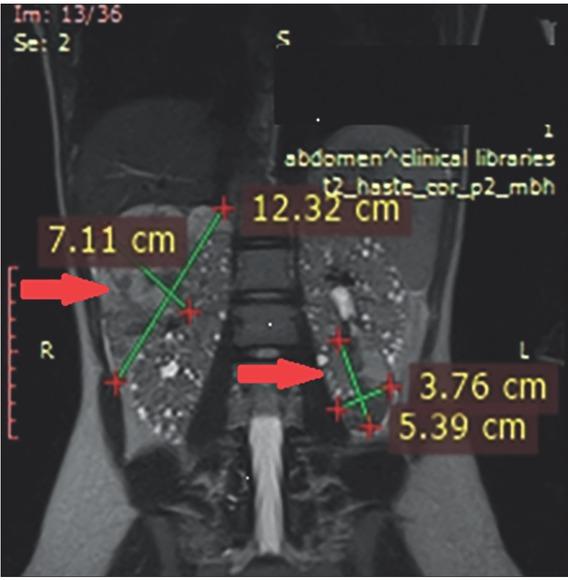

Figure 1